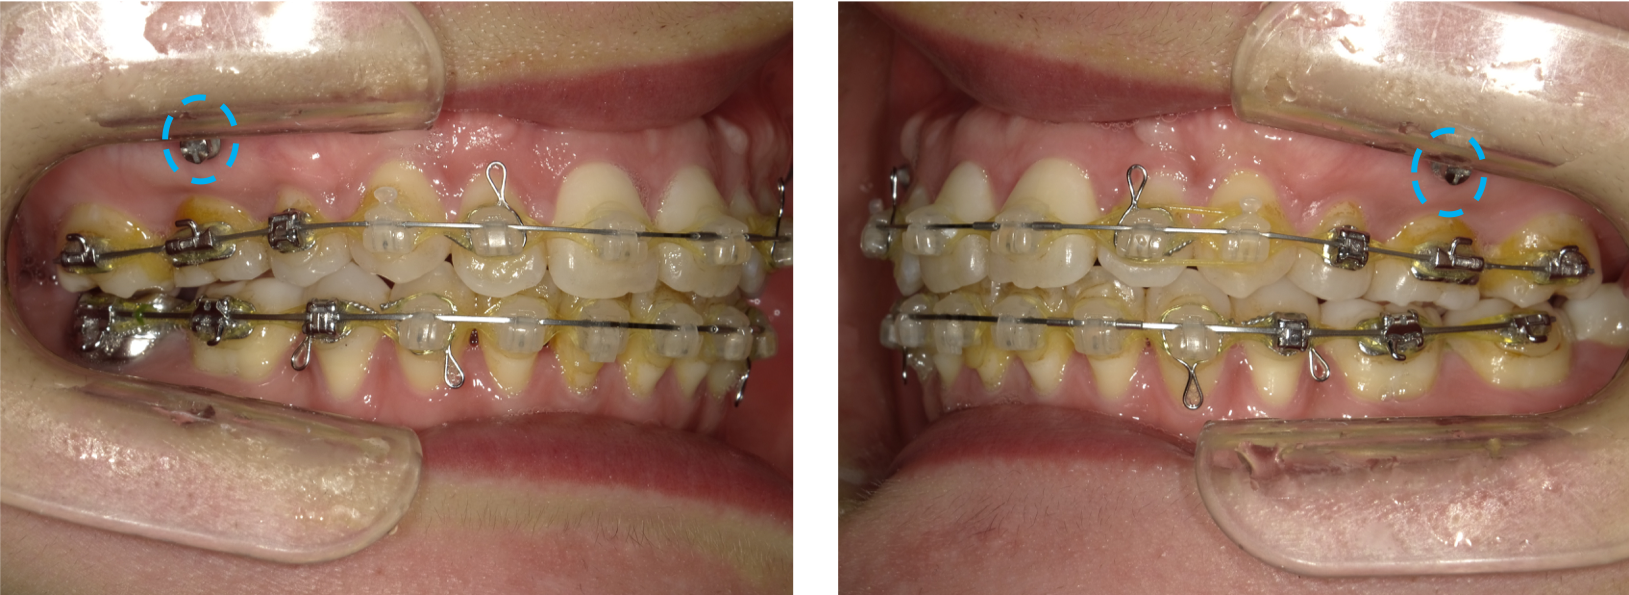

【治療中】

上顎左右4番、下顎左右5番の計4本を抜歯をし移動させるスペースを確保したあと、アンカースクリュー(水色の◯の箇所)を併用し、前歯を後方へ移動させました。

※関連記事:アンカースクリュー特集>>